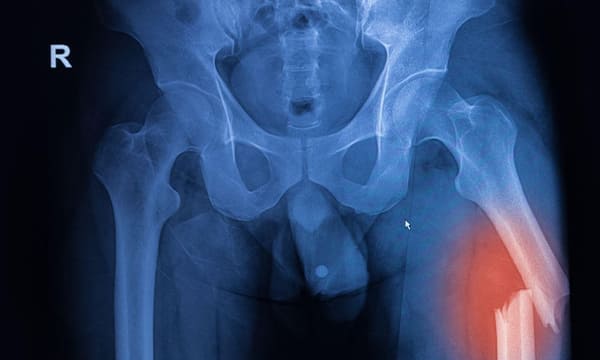

Intramedullary Nailing (IM Nailing) is a stabilisation technique used for fractures of long bones, such as the femur, tibia, and humerus. At Melbourne Orthopaedic Clinic, our team uses this advanced method to provide patients with strong, internal support that promotes bone healing and allows early mobility. This procedure is effective for treating fractures with minimal soft tissue disruption.

Intramedullary Nailing involves inserting a metal rod, or nail, into the central cavity of a long bone (the medullary canal). The nail is designed to keep fractured bone segments aligned and stable during healing. Once placed within the bone, the nail is secured with locking screws at each end to hold the fragments in place.

- Long Bone Fractures: Especially fractures of the femur (thigh bone), tibia (shin bone), and humerus (upper arm bone).

- Long Bone Fractures: Particularly in weight-bearing bones where stability is crucial.